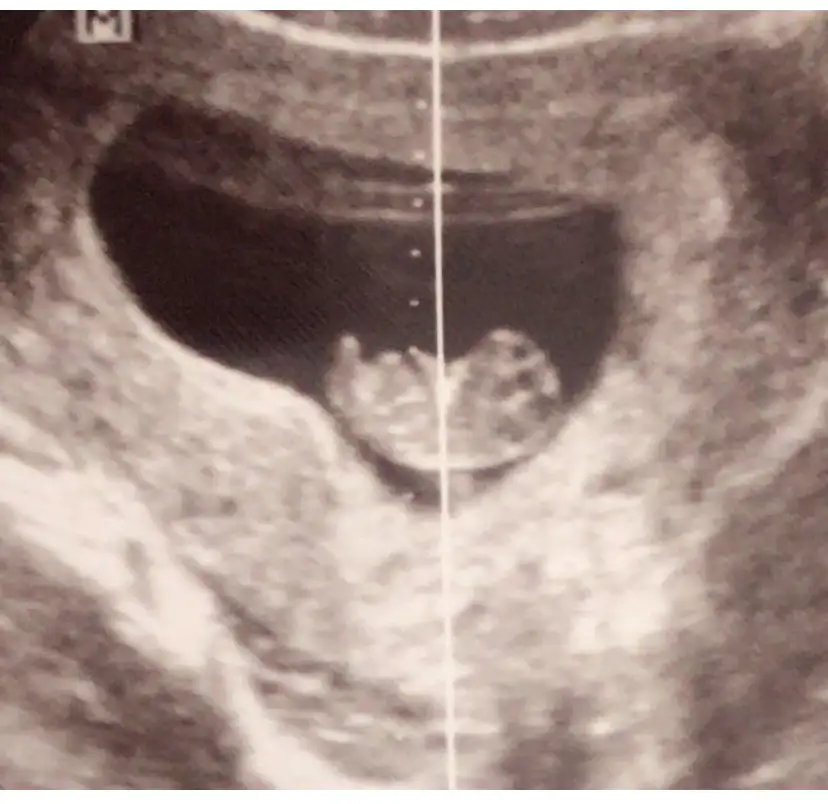

Tatlim bakarsan sevinirimSelam kizlar yorum yaparsaniz sevinirim.

Bu usgde ise 11-12

9 haftalik burda